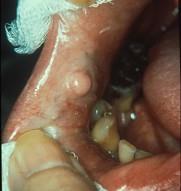

组图为口内纤维瘤的外观,关于此病的描述不正确的是 ( )

组图为口内纤维瘤的外观,关于此病的描述不正确的是 ( )![]()